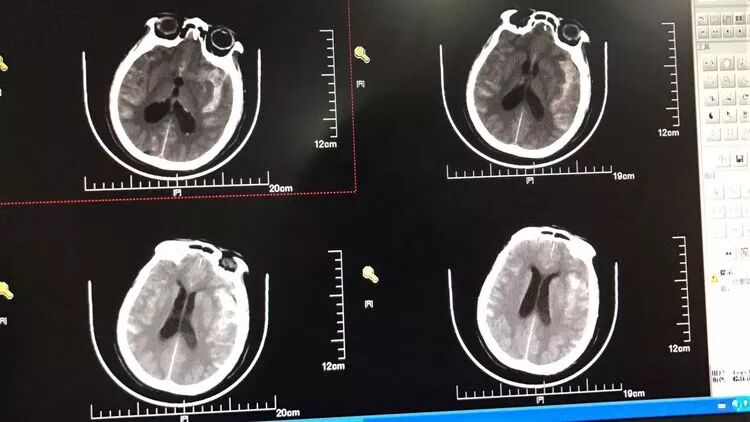

女,73岁,蛛网膜下腔出血量还挺多的,H-H 分级4级

造影显示左侧后交通动脉瘤

椎动脉造影没发现大脑后动脉,双侧的大脑后动脉都是由颈内动脉-后交通动脉发出,双侧胚胎型大脑后动脉